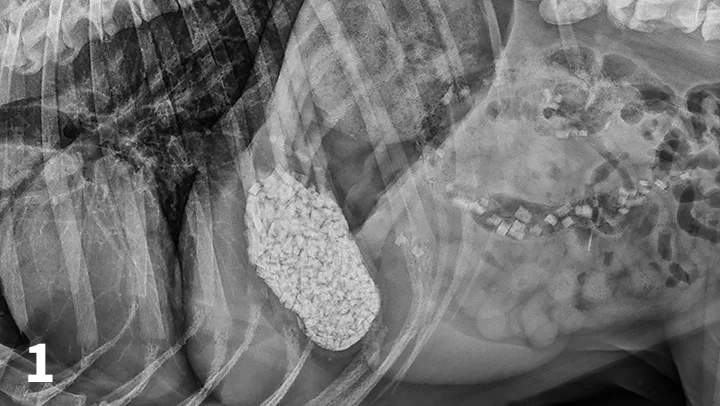

CBC reveals a leukocytosis (19.34 103/L; range, 5.10-14.00) characterized by a lymphocytosis (5.5 103/L; range, 1.4-4.6) and a mature neutrophilia (13.10 103/L; range, 2.65-9.80) with a mild thrombocytopenia (171 103/L; range, 147-243). A pancreatic-specific lipase is elevated (580 g/L; range, 0-200 g/L) and consistent with pancreatitis. Abdominal radiographs (Figures 1-3; See below) reveal a moderately distended stomach that contains a large number of irregularly shaped mineral opacities. Additional mineral opacities are present in multiple small intestinal segments as well as the colon. There is also a mild decrease in serosal detail in the mid-abdominal region.

A right lateral abdominal radiograph taken approximately 24 hours after glass ingestion. Multiple, irregularly shaped mineral opacities are present within the stomach, small intestine, and colon.